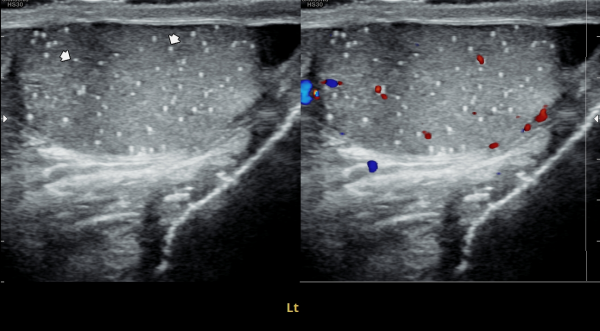

수년전부터 우측 고환의 통증으로 내원 당일 검사한 초음파 사진상 고환의 미석증이 관찰되는 사진입니다.(NIH:24)

The patient presented with right testicular pain for several years.

On the initial ultrasound examination performed on the day of the visit, the right testis shows multiple echogenic foci without acoustic shadowing, consistent with testicular microlithiasis.(NIH:24)

주 2회 14주 동안 정관과 사정관, 정낭 그리고 전립선의 표적 치료후 치료되고 있는 우측 고환 미석증들의 초음파사진입니다.(NIH:13)

This ultrasound image shows improvement of right testicular microlithiasis after targeted treatment of the vas deferens, ejaculatory ducts, seminal vesicles, and prostate.

The treatment was performed twice a week over a period of 14 weeks, and the previously observed tiny calcifications in the testis are gradually improving, suggesting better circulation and recovery of the reproductive tract.(NIH:13)